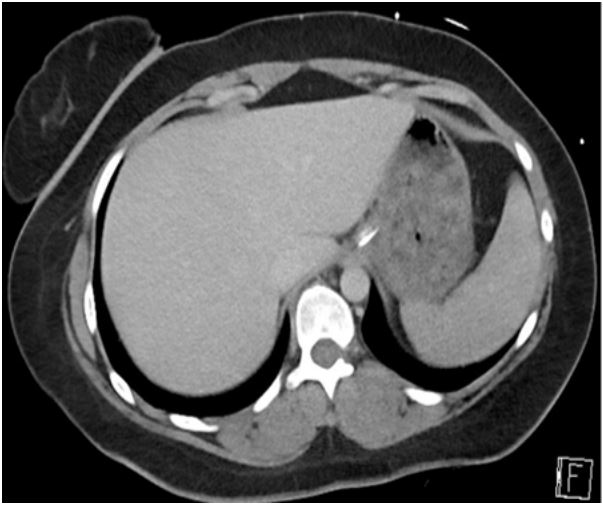

New Zealand National Poison Centre was consulted 30 hours after her initial presentation. The ingested dose of 309 mg/kg of venlafaxine and 224 mg/kg of lamotrigine significantly exceeded the intervention threshold, (12.5 mg/kg and 30 mg/kg for venlafaxine and lamotrigine, respectively) [7,8]. Abdominal cross-sectional imaging and/or urgent gastroscopy was recommended to assess/remove any remaining pill burden. Abdominal Computed Tomography (CT) 36 hours after the initial presentation revealed large pill concretion within gastric lumen (Figure 1). Urgent gastroscopy using therapeutic endoscope (GIF-2TH180, dual channel 3.7 mm and 2.8 mm diameter, Olympus Medical, Japan), found a large conglomerate of tablets in the stomach (Figure 2). Pill retrieval was attempted with a retrieval basket (Meditalia® 30x60 mm Loop Net, Italy) and a polypectomy snare (SnareMaster Plus, 10 mm, Olympus Medical, Japan). The procedure was technically challenging due to the large, compact nature of the concreted pharmacobezoar. The pharmacobezoar could not be easily broken down or removed and significant amount of pill burden remained. A last resort laparotomy was then contemplated to aid gastric decontamination, but the patient was deemed hemodynamically too unstable. She continued to deteriorate despite all available supportive measures and died a few hours later

Massive venlafaxine overdose is associated with delayed gastric emptying. This, along with the adhesive gelatine capsule of the sustained release drug preparation could lead to the pharmacobezoar formation and its solid, concrete-like nature (concretion) [9]. In case 1, this was seen in stomach 36 hours after ingestion, significantly longer than a standard solid gastric emptying time of around 4 hours. Resultant prolonged absorption can cause delayed or prolonged toxicity [6]. We are uncertain of the effect of co-ingested lamotrigine.